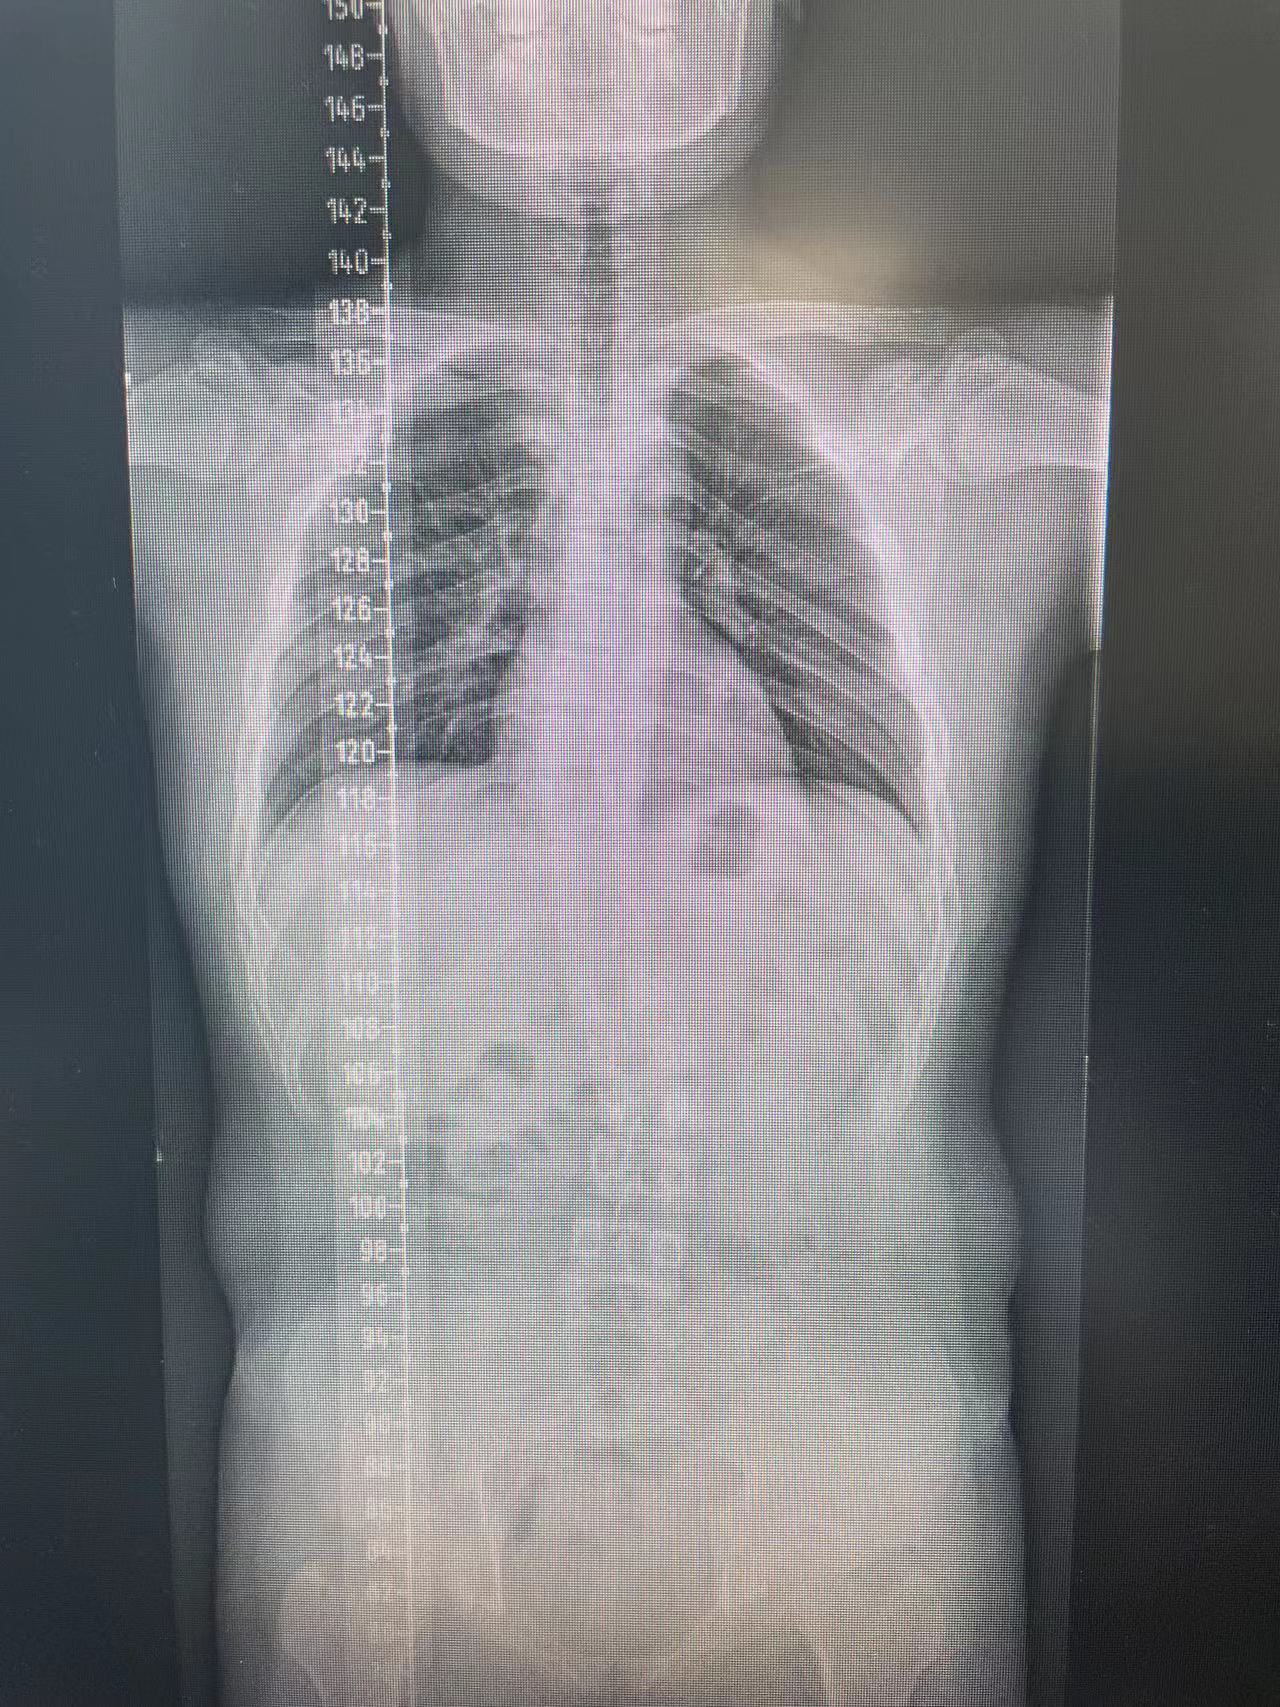

患者杨某,15岁,一年前在家中行走不稳,未及时给予系统治疗,现双下肢僵硬、无力症状明显,影响正常生活,遂前来91直播 脊柱外科中心D区接受住院治疗。

脊柱外科中心D区辛大奇、王东海、孙洪岩医疗团队完善患者术前检查后,明确诊断为胸12半椎体侧后凸畸形,经过积极与胡侦明教授沟通、讨论后,共同为患者制定手术方案,为患者施行先天性脊柱侧弯、半椎体侧后凸畸形截骨矫形+植骨融合内固定术。